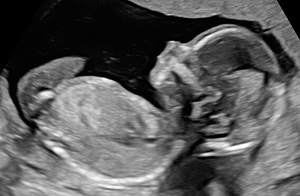

Toch lukt het niet altijd om het perfecte plaatje te schieten, er kunnen namelijk altijd beperkingen meespelen die afbreuk doen aan de kwaliteit van de beelden.

Je kunt hierbij dan denken aan:

- Een ongunstige of diepe ligging van het kindje in de baarmoeder. Bijvoorbeeld als jullie kindje het gehele onderzoek met het gezichtje naar jouw rugzijde ligt gedraaid of dat jullie kindje zich achter handjes/voetjes of navelstreng verstopt. Ook speelt de afstand tussen de probe en jullie baby een belangrijke rol, hoe groter deze afstand hoe minder scherp de beelden kunnen zijn.